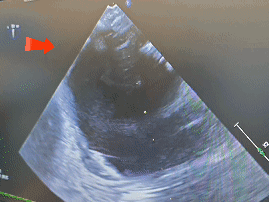

双封堵器释放后超声

心脏位于左侧胸腔,心尖指向左下。房室连接正常。右心较术前减小。左室壁不增厚,运动未见明显异常。主动脉瓣形态结构未见异常;二尖瓣形态结构未见异常;三尖瓣形态结构未见异常。

CDFI:AR(-),MR(少量),TR(少量)。房间隔中部探及两处封堵器回声,房水平未见明显分流。室间隔连续完整,室水平未见明显分流。肺动脉内径不增宽。升主动脉内径23mm。心包腔内未见明显液性暗区。

《常见先天性心脏病介入治疗中国专家共识》指出:对于存在2个ASD,但缺损间距≤7mm,可选择1枚封堵器闭合;多个缺损的间距>7mm,无法采用1枚封堵器实施介入治疗,需要选择2~3枚封堵器分别闭合[1]。本例食道超声示两处缺损(回声中断8.06mm,分流束宽5.63mm),两个缺损之间相距8.48mm,术中通过超声精准指导,先植入BDASD-I16封堵器封堵8.06mm缺损,再测量第二个缺损约5mm后,植入BDASD-I10封堵器,术后即刻超声显示,两枚MemoSorb可降解封堵器位置形态理想,无残余分流,封堵成功。